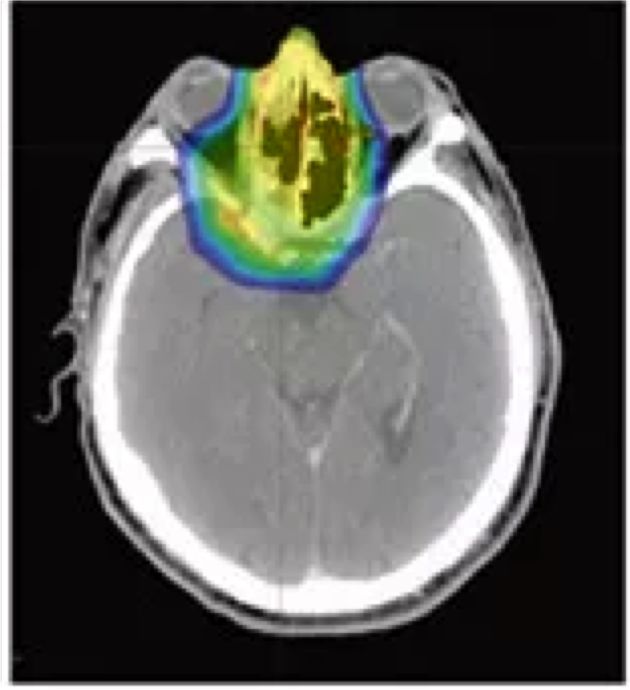

比如下图的头CT照片中,黄绿色部分是一个神经肿瘤,形态不规则,深度也不规则。

利用传统3D放疗技术可以把主要能量(红黄色部份)集中在肿瘤区域。但仍然有一部分低能量(蓝绿色)会波及到周边正常组织。即便3D照射技术很成熟,但由于伽马、x射线的本身特性,这种能量外溢不可避免。

当我们把射线换成质子和重离子线后,问题迎刃而解。调强质子治疗(IMPT)就是利用质子和重离子射线进行适形治疗。

这样对比下来,可以清楚的看出,对于不需要照到的地方,布拉格峰效应几乎不会损伤周围组织,不仅可以在癌症区域照射最大能量,同时有效地保护周边器官。